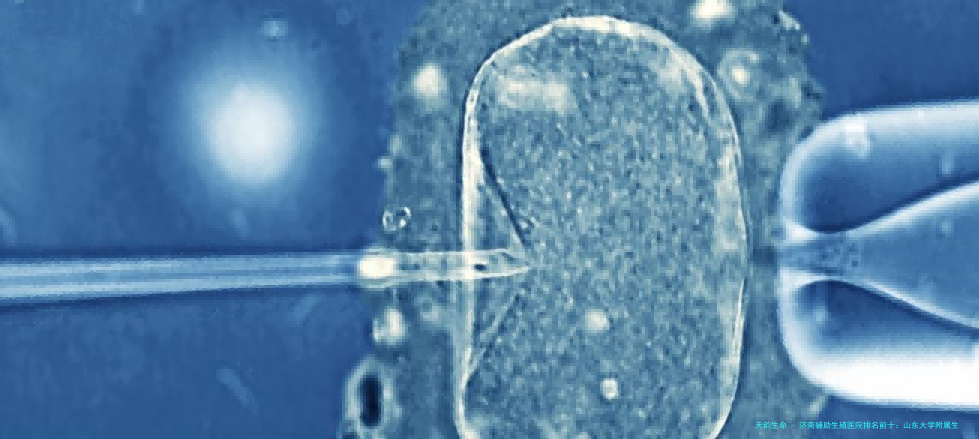

对于40岁以上的准双亲,我个人的概念是,应首先考虑技术积淀深厚、实践室水平的医院。因为年龄是影响的核心要素,一个安定、的胚胎实验室往往能带来“质”的差别。